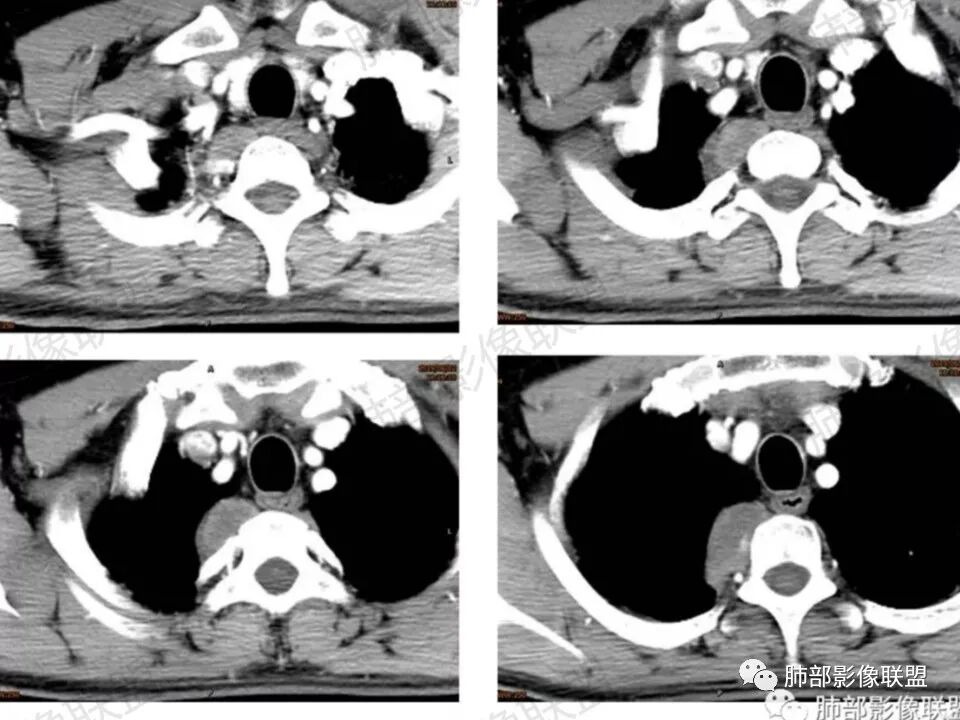

男,45岁,反复背痛3年;病程长,发展缓慢;后纵膈,与脊柱关系说不清;强化明显,有分区;诊断:神经源肿瘤;良性鉴别:间质来源肿瘤。

患者,男性 45岁,反复背部疼痛3年。右侧后纵膈脊柱旁软组织影,匍匐样生长,临近骨质未见破坏征象,软组织局限性隆起,椎间孔未见明确扩大。增强呈渐进性升高,内部强化不均匀,未见坏死、囊变。结合病史,总体考虑良性病变,神经来源,神经鞘瘤可能。

这个病例定位肺外没问题,病灶呈宽基底,见明显的胸膜掀起征,定位胸膜或右后纵隔来源,而且肿块提示肋间动脉穿行,脏层胸膜来源可能性不大(脏层胸膜由肺动脉及支气管动脉供血),那就是壁层胸膜跟纵隔来源,但是图像上有2个层面是胸膜外间隙有受压推移,所以壁层胸膜来源也不考虑;病灶是渐进性强化,常见的就是间叶来源含有梭形细胞的软组织肿瘤跟后纵隔常见的神经源性肿瘤鉴别,那如何在后纵隔的大山里拨开云雾找到我们想要的答案呢?那小编在这里先理出几个问题:

问:这个病例病灶确实邻近椎间孔生长,除了神经源性肿瘤会向椎间孔方向生长,还有什么肿瘤会有这种行为?这个病灶整体形态呈扁平不规则,周围骨质未见破坏,就一定是良性吗?    答:这个病灶明显嵌入式生长,往往提示病灶柔软或有侵袭性,而神经鞘瘤往往有包膜,有张力,典型的形态往往呈类圆形、“逗点形”或“哑铃型”横向延入某一椎间孔内;神经节细胞瘤虽然可以比较柔软,但是具有大量粘液基质,动静脉期强化不明显,延迟强化轻度增强,加之没有钙化,故符合点不多;此外比较柔软的肿瘤如淋巴瘤,但是周围没有肿大淋巴结不太考虑;本例形态不规则的实性肿块,没有明显骨质破坏,倾向具有侵袭性的间叶来源的肿瘤。

答:神经源性肿瘤的解剖位置及形态很重要—沿神经干方向生长走行。后纵膈内神经鞘瘤最常见的是神经根出入椎间孔处,并可沿着肋间神经方向分布,所以后纵膈神经鞘瘤通常横径大,上下径小,这个病例明显上下径长,所以不符合神经鞘瘤;神经节细胞瘤可沿着椎旁上下方向分布(参见上图黄色梭形的神经节),所以表现为上下径长,虽然生长方式符合,但是节细胞瘤以粘液为主,易钙化,该病例成分及强化方式不符合。